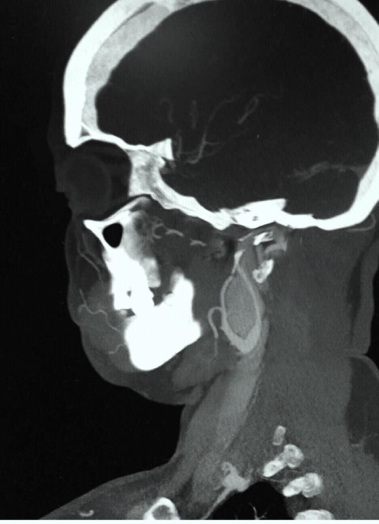

Initially, the diagnosis of delirium overlapping with depression was made by the psychiatric evaluation and the case was forwarded to the academic board for an expert opinion. Although, the patient was conscious and but not well oriented in time and space. Psychiatrist’s opinion also suggested that the personality changes may not be associated with any major lesion in the brain but a possibility of low perfusion of certain focal areas can be associated with such symptoms. It was difficult for a particular psychiatric condition so further evaluation was requested. On careful re-evaluation of the symptoms, a vascular surgeon consult was requested, which led to magnetic resonance angiography (MRA) and extensive head and neck imaging of the patient. The figure 1 shows sagittal section of computerized tomography (CT) scan revealing a tumor-like mass on the bifurcation of the carotid artery on the right side with compression of the vascular lumen (15.5 x 31.5 x 34.8 mm).